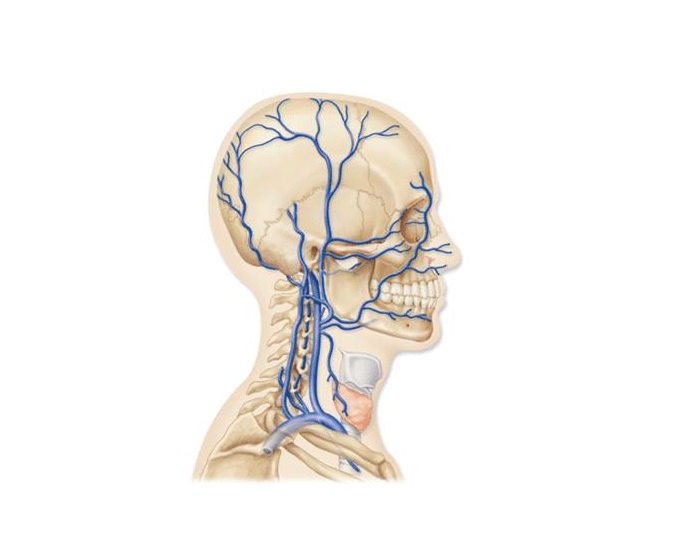

Анатомия внутренней яремной вены: КТ изображения